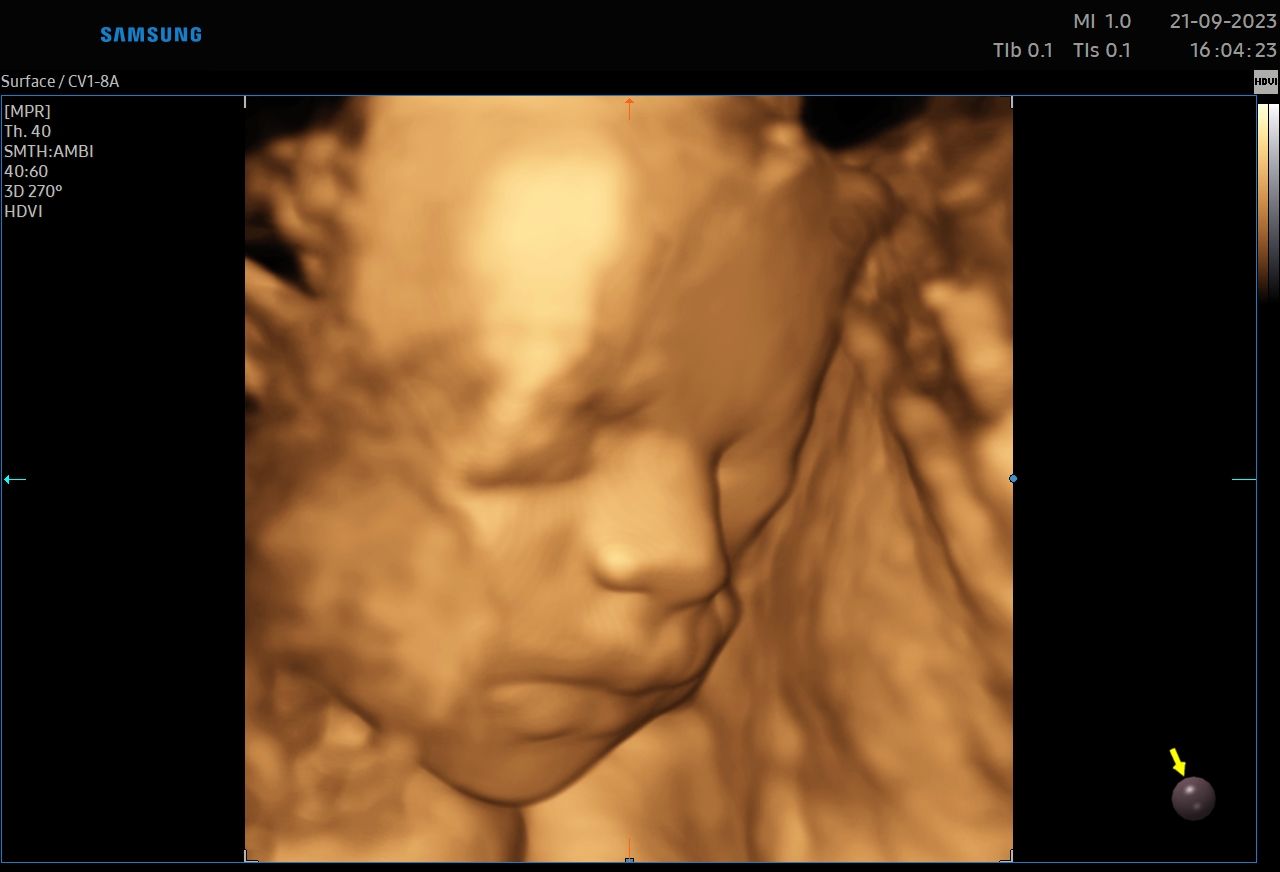

:-) Jestem lekarzem specjalistą w zakresie ginekologii i położnictwa , w ramach prowadzonej praktyki ginekologicznej staram się świadczyć kompleksowe porady lekarskie najwyższym poziomie ,w oparciu o najwyższe standardy jak i przy pomocy najnowszego sprzętu medycznego. W trakcie pracy zawodowej uzyskałem kolejno tytuły specjalisty I stopnia , a później specjalisty II stopnia , a także uzyskałem dodatkowe uprawnienia

CERTYFIKAT BADAŃ PRENATALNYCH POLSKIEGO TOWARZYSTWA GINEKOLOGÓW I POŁOŻNIKÓW

CERTYFIKAT BADAŃ PRENATALNYCH FMF ( FETAL MEDICINE FOUNDATION - LONDYN )

W ramach praktyki wykonuję pełen zakres badań ultrasonograficznych w zakresie ginekologii jak i położnictwa wraz z badaniami prenatalnymi , badaniami ultrasonograficznymi piersi .

Zdjęcia i filmy